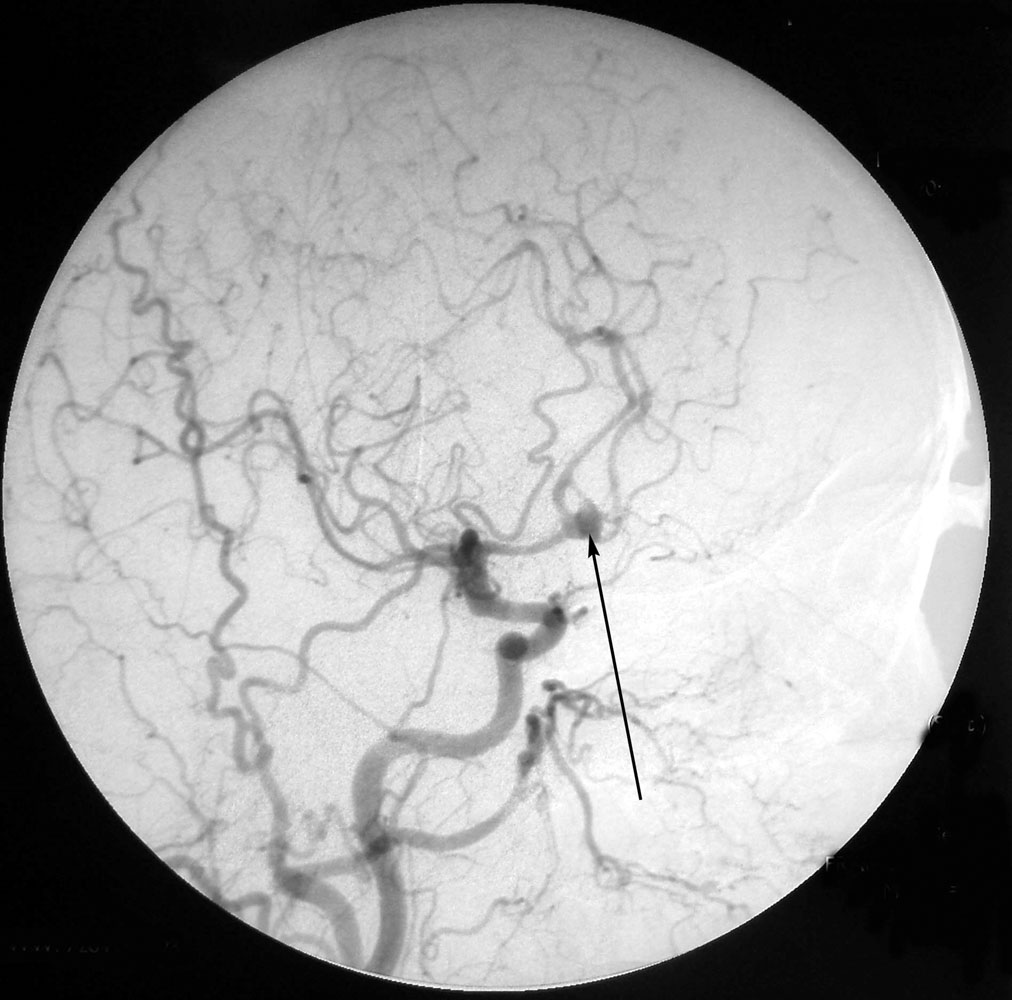

Снимки и иллюстрации микроаневризм сосудов головного мозга